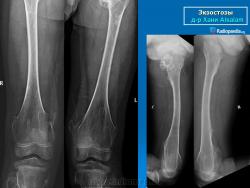

Локализация остеохондромы: частота поражения отдельных костей различна; нижний коней бедренной кости, верхние отделы плечевой и большеберцовой костей поражаются более чем у половины больных. На всем протяжении остеохондрома покрыта надкостницей. Она может быть обнаружена и в других костях, за исключением костей лицевого черепа. Все же поражение костей позвоночника, кистей рук и стоп встречается редко. При рентгенологическом исследовании видна типичная картина узкого или широкого выроста вблизи эпифизарной части пораженной кости. Обычно плотность узла неоднородная, имеются многочисленные плотные участки, соответствующие обызвествленным хрящевым долькам. Хрящевая «шапочка» большей частью не определяется, поскольку хрящ остается необызвествленным. Она может быть выявлена только при магнитно-резонансной томографии.